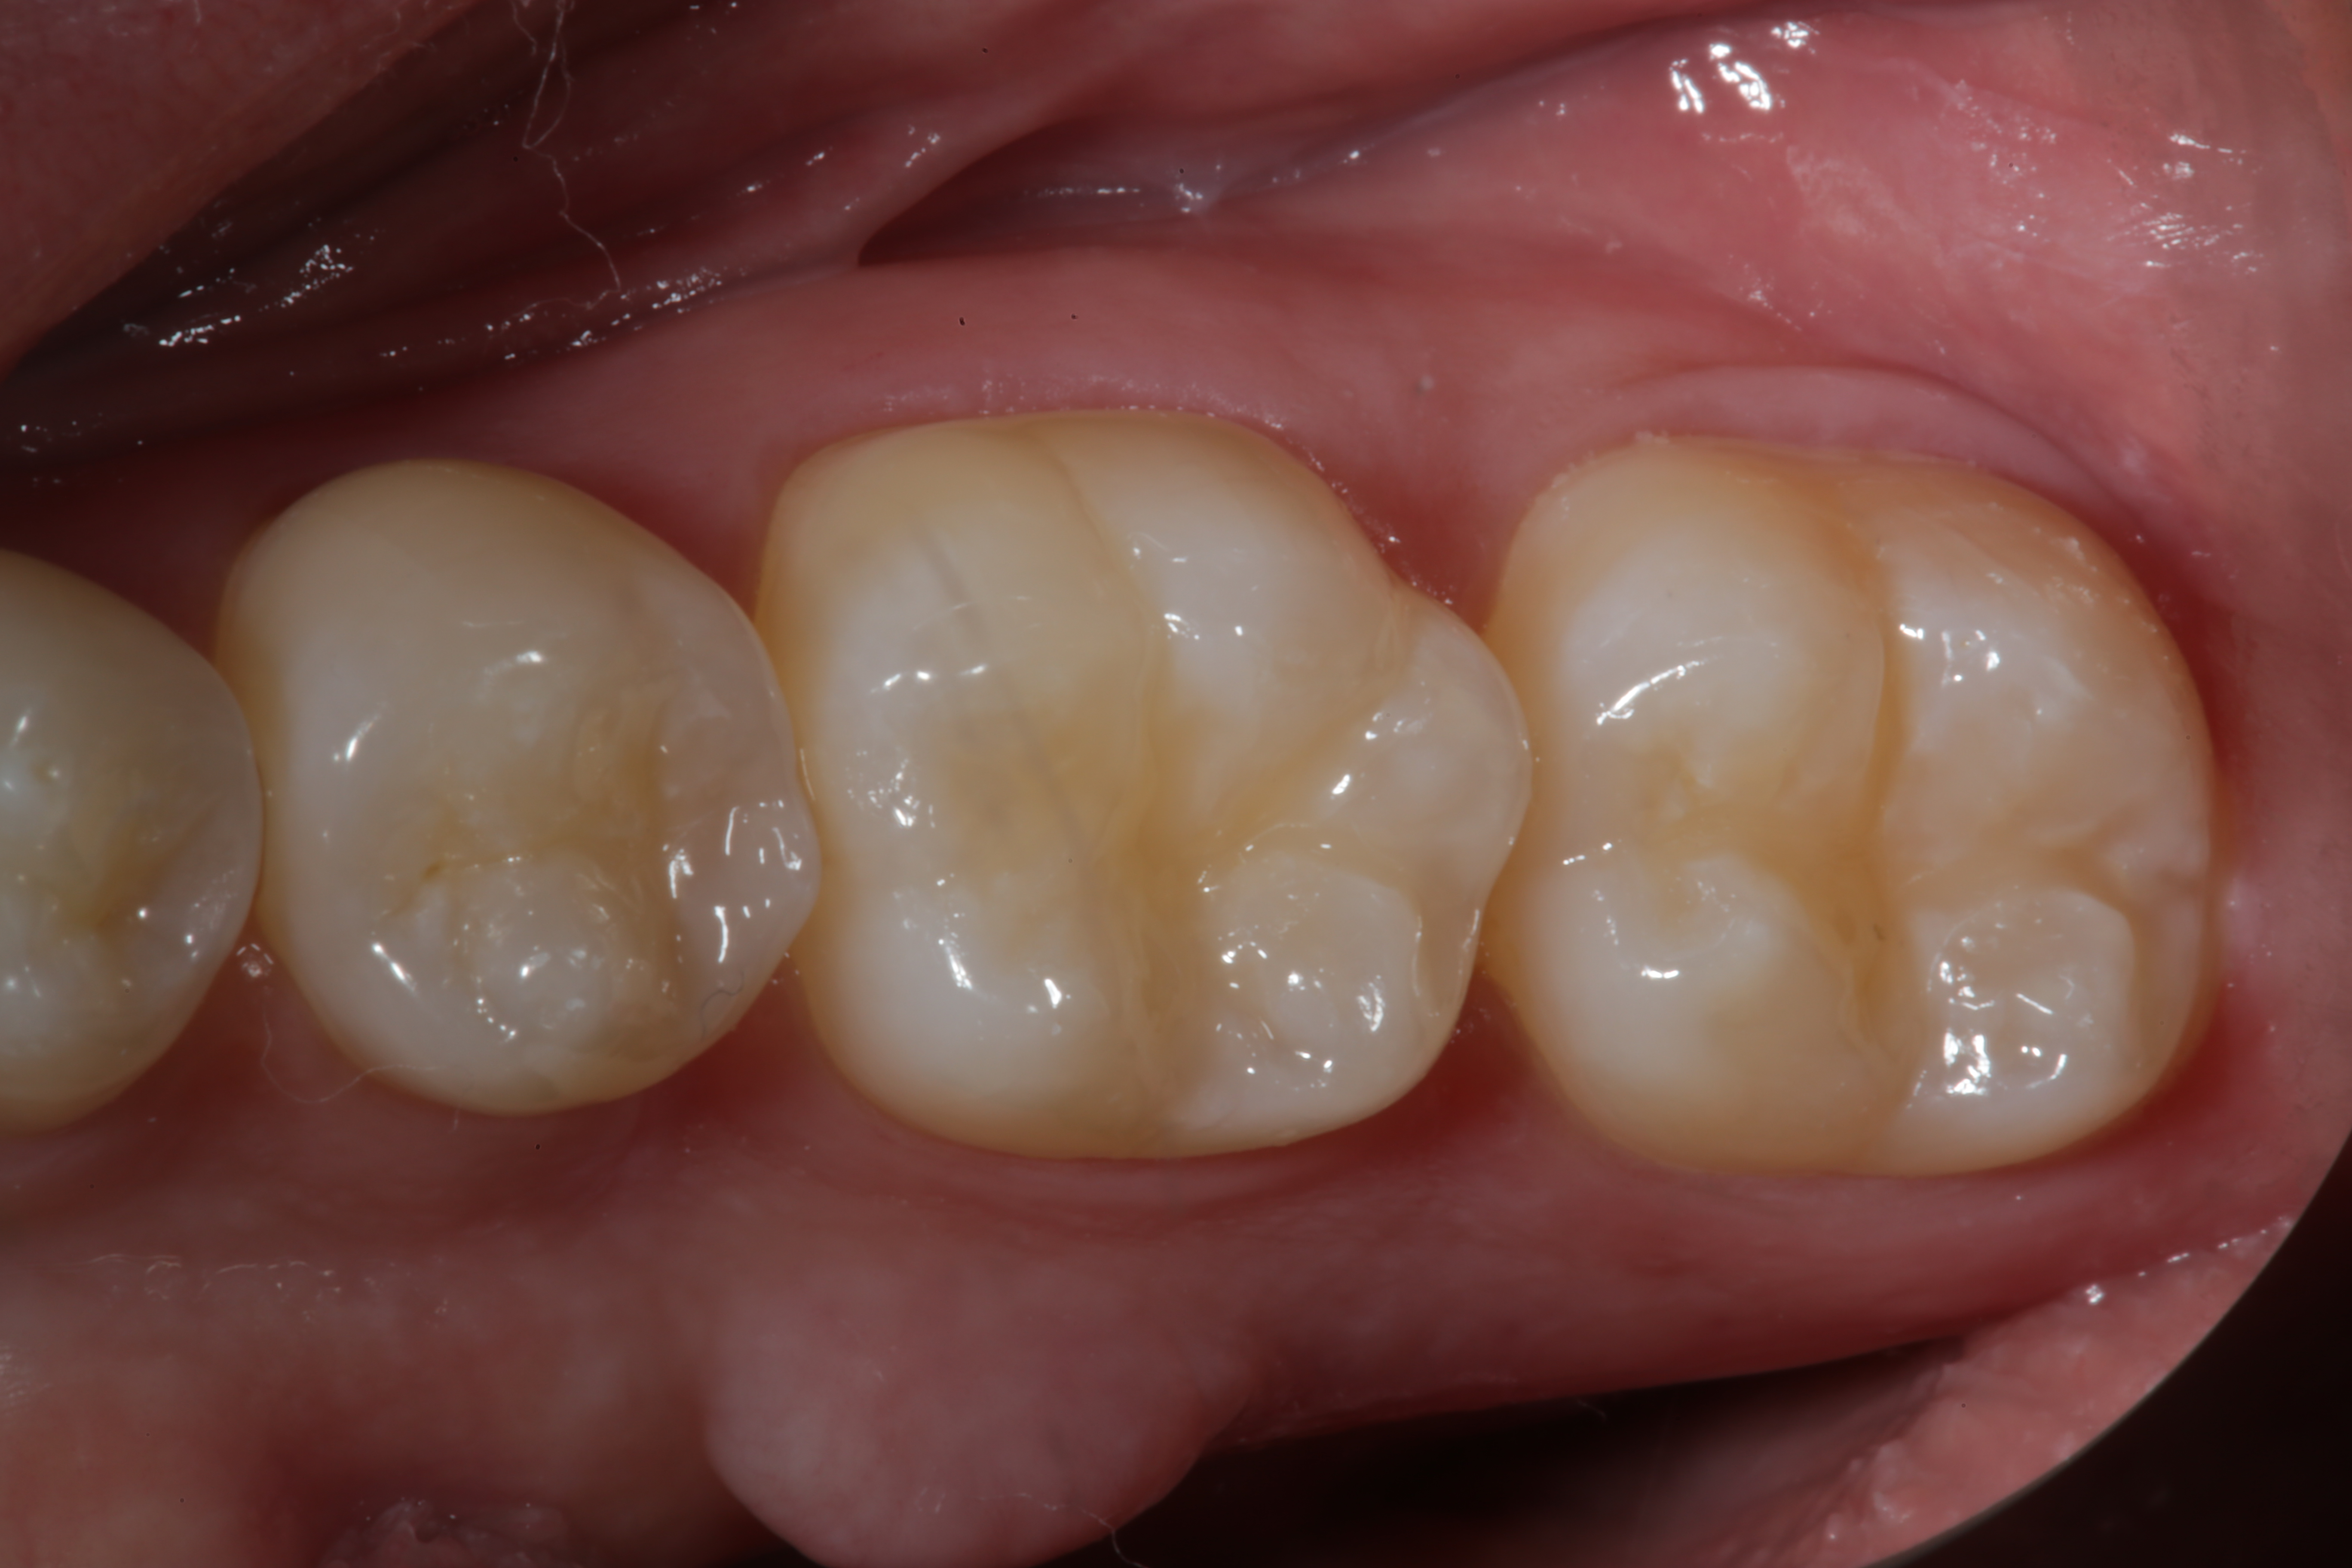

Nanohybrid and nanofilled paste composites that are typically used for tooth-colored restorative procedures are more highly filled and polishable than previous generations of composite materials because of advances in polymer chemistry and materials science. These materials are often called universal because they can be used in the posterior regions as well as in anterior, esthetic areas of the oral cavity. Many of these restoratives contain nanofiller technology and are formulated with Nanomer and nanocluster filler particles. Nanomers are separate, discrete nano-agglomerated particles of 20 to 75 nm in size, and nanoclusters are loosely bound agglomerates of nano-sized particles. The combination of Nanomer-sized particles and nanocluster formations reduces the spacing of the filler particles, thus creating the ability to increase filler capacity (better physical properties) while still having the ability to polish extremely well (less plucking, smoother surfaces). Nanohybrids therefore have improved physical properties over the earlier generations of microhybrid composites, while having increased luster and polish retention (Figure 12 through Figure 19).26-28

Fig 19. The completed Class IV Giomer restoration is seen on tooth No. 9 from the facial aspect. Note the esthetic quality of this layered anterior composite restoration as it compares with the surrounding natural teeth.

Figure 19